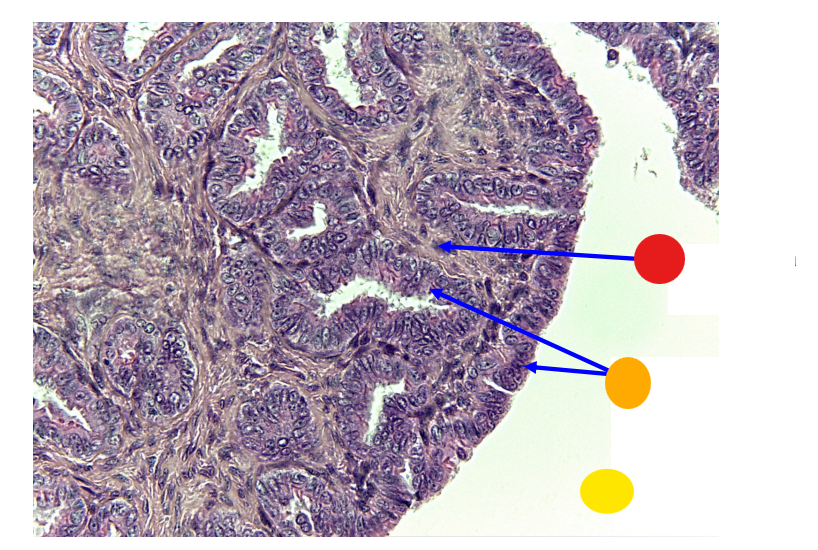

red

primordial follicles

red

primary follicles

red

tunica albuginea

orange

primary oocyte

yellow

primordial follicles

red

granulosa cells

orange

primary oocyte

what is this

primary follicle